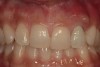

From a clinical perspective, the primary challenge was the development of an esthetic emergence of the dental implant-supported crown restoration. Maintenance of the soft-tissue dimensions, therefore, was critical to the treatment success. In an effort to optimally maintain the ridge form, a connective tissue graft harvested from the palate39,40 was placed over the collagen membrane to augment the soft tissues. Then, the buccal flap was advanced to achieve primary closure. Postoperative healing proceeded uneventfully. The overlying soft tissue exhibited rapid clinical closure and healed with minimal evidence of the surgical procedure. The clinical outcome was also consistent with development of the desired ridge form. Cone-beam computed tomography imaging revealed an alveolar ridge form that was optimal for implant placement at 5 months post-treatment. The radiographic density of the augmented region was similar to the adjacent native bone, with no discernable interface between native and apparent new bone, consistent with integration and remodeling. Surgical re-entry for implant placement revealed the optimal ridge form (Figure 6 ). The implant was allowed to integrate for 5 months prior to the healing abutment placement and interim restoration. The overcontoured soft tissues enabled surgical sculpting to achieve the desired contour for the restorative emergence. A highly acceptable esthetic result was achieved. With preservation of the marginal and papillary gingival contours (Figure 7 and Figure 8 ); the radiographic presentation was consistent with normal bone remodeling and implant integration.

Figure 8  Marginal and papillary gingival contours were well preserved using this technique.

Figure 8